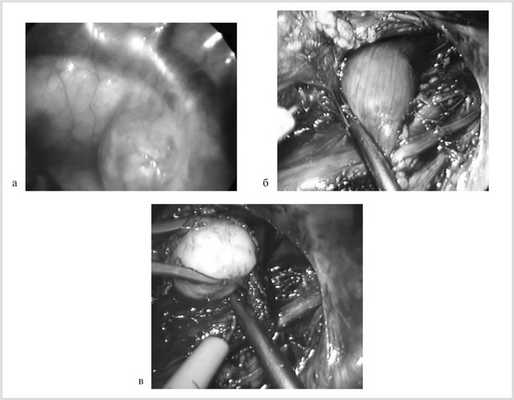

У 6 (66,7%) больных, оперированных торакоскопически, опухоль контурировалась через медиастинальную плевру или становилась доступной после ее рассечения (рис. 2, а, б).

Рис. 2. Фрагмент операции: лейомиома пищевода контурируется через медиастинальную плевру (а), после медиастинотомии (б); внеслизистое выделение лейомиомы пищевода (в).

У 3 (33,3%) пациентов для интраоперационного позиционирования опухоли, диаметр которой не превышал 1 см, выполнена фиброэзофагоскопия с эффектом трансиллюминации. В 1 случае визуализация опухоли стала возможной после клипирования и пересечения непарной вены.

На уровне опухоли производили мобилизацию пищевода на протяжении 4—5 см до ½ его полуокружности. Эндокрючком с использованием монополярной диатермокоагуляции над опухолью выполняли продольную миотомию. Опухоль в капсуле выделяли из окружающих тканей без повреждения СО (см. рис. 2, в).